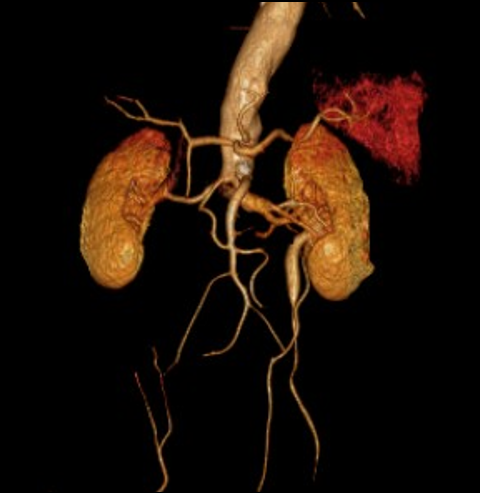

重建方式选择:包括双筒对吻支架、EVAR腔内移植物、CERAB技术等。

分支动脉保护:特别注意保护肾动脉和内脏动脉。

主髂动脉闭塞的重建方式

双筒对吻支架:使用BMS或覆膜支架。

EVAR腔内移植物:一体化或分叉型。

CERAB技术:覆盖主动脉分叉区域的腔内重建技术。